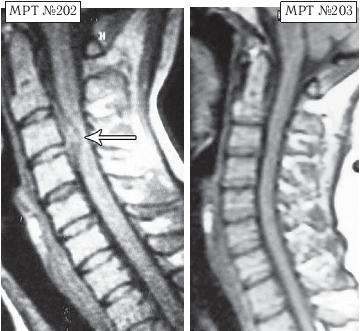

На МРТ № 202 наблюдается состояние шейного отдела позвоночника: секвестрированная грыжа межпозвонкового диска в сегменте CIII—CIV с миграцией секвестра, как в каудальном (вниз), так и в краниальном (вверх) направлении, с экскавацией дурального мешка (сдавлением спинного мозга) в сегменте CIII—CIV, сглаженность лордоза, стеноз и так далее.

На МРТ № 203 наблюдается состояние шейного отдела позвоночника после двух курсов лечения методом вертеброревитологии: отсутствие грыжи межпозвонкового диска в сегменте CIII—CIV, отсутствие стеноза, и самое главное, восстановлена биомеханика, то есть восстановлен естественный, физиологический лордоз до состояния нормы.